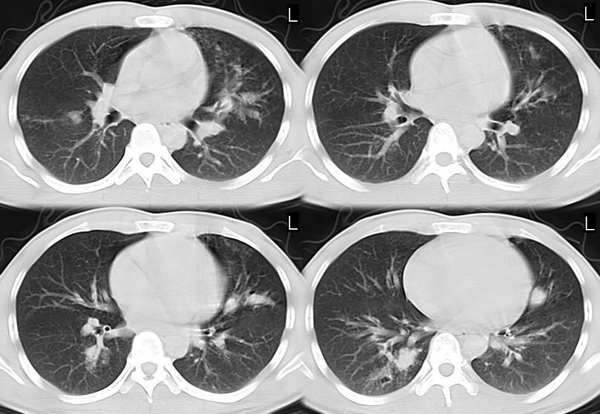

男,21岁,一年前确诊肺结核(未见年前照片),经抗结核治疗出院。2005年9月26日照片与2006年3月1日照片对比,病变反而增多,但病人症状不明显.疑惑?

2005年9月26日照片